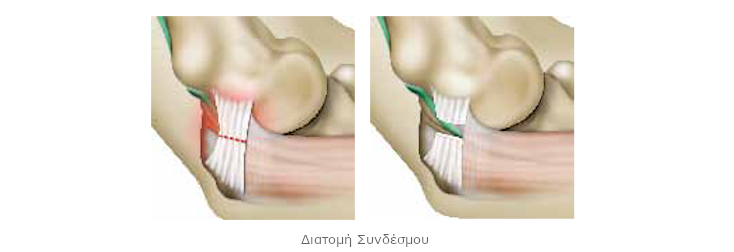

Διάφορα στοιχεία μπορεί να πιέζουν το ωλένιο νεύρο. Συνήθως, οφείλεται σε πάχυνση του συνδέσμου της αύλακας. Αυτή η περίπτωση παρουσιάζεται σε αυτό το έντυπο.Ο χειρουργός απελευθερώνει το νεύρο. Στην ιατρική γλώσσα, αναφέρεται ως νευρόλυση.

Η βασική επέμβαση

Μετά την τομή στο δέρμα, ο χειρουργός αποκαθιστά τη βλάβη στον ιστό που κλείνει την αύλακα του ωλενίου νεύρου. Πραγματοποιεί τομή και συνήθως, αφαιρεί ένα μικρό τμήμα. Το νεύρο δε συμπιέζεται πια: απελευθερώνεται.